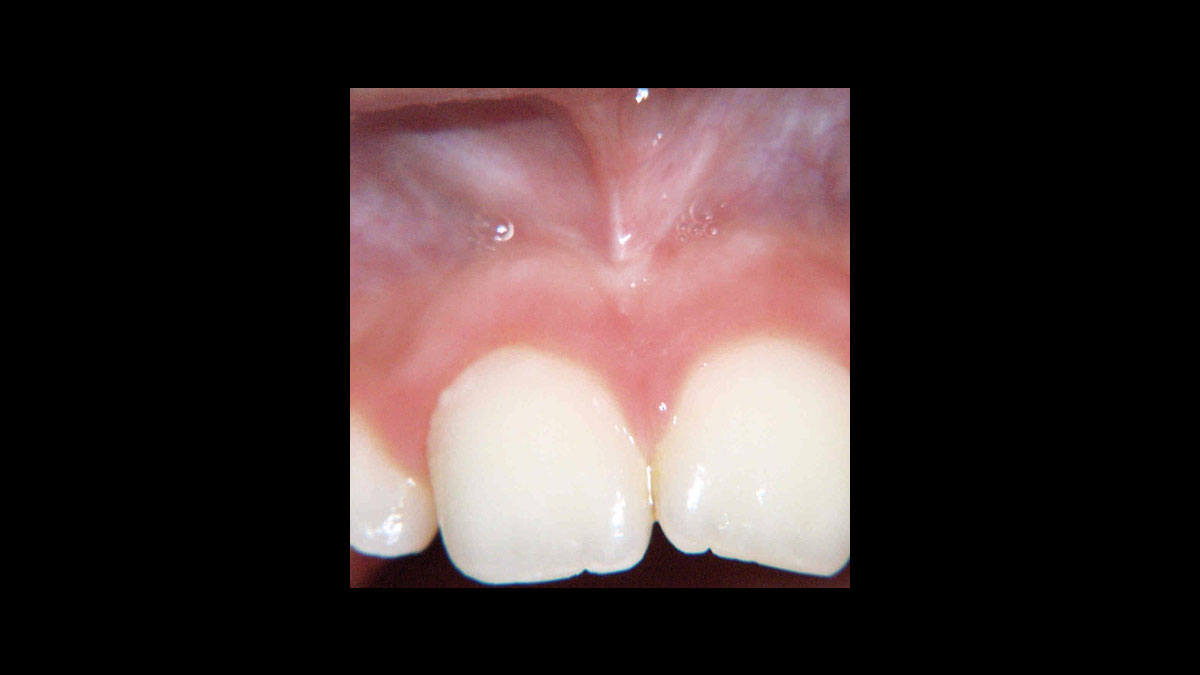

Frenectomy